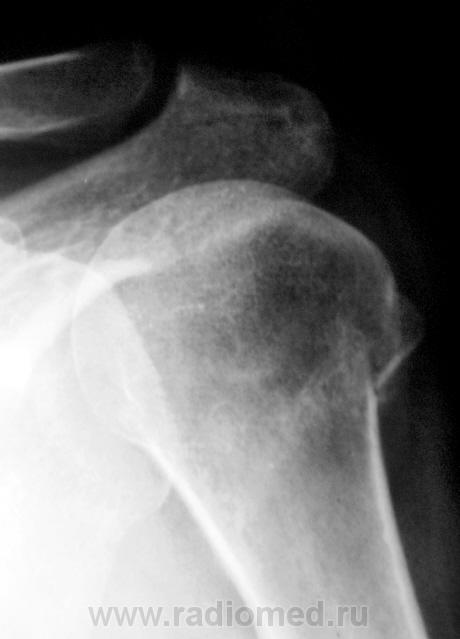

Вот эта штука уж очень похожа на молодую костную мозоль.

4.p1270032ab1.jpg

lupan wrote:

Мне кажется, что это не мозоль, а "смятая" костная ткань за счет вколочения

Мы, тоже склонились к вколоченному (сколоченному) перелому.